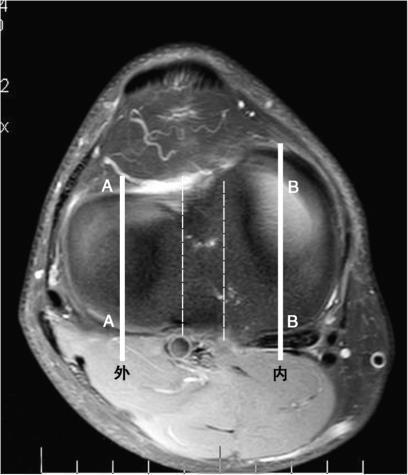

图5-6 选取测量平面

分别选取内侧平台或外侧平台中间层面测量内侧或外侧平台后倾角,AA为外侧,BB为内侧。